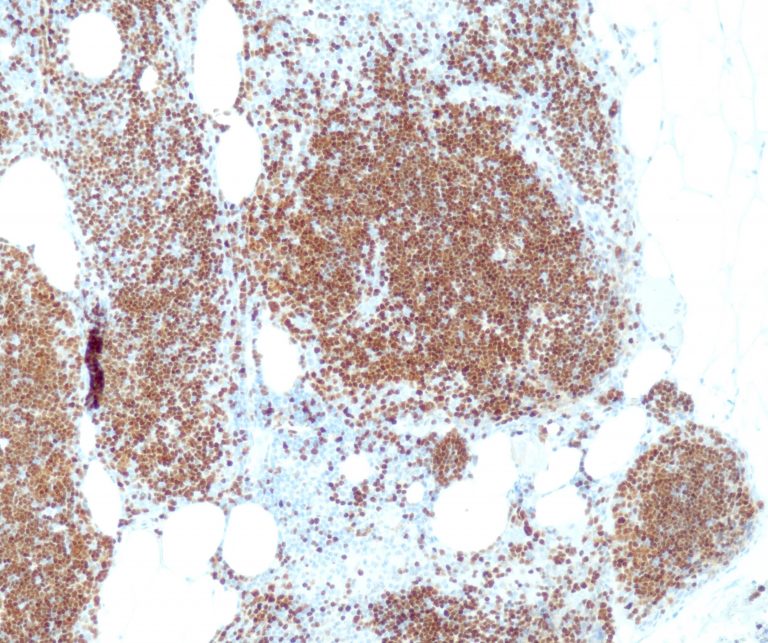

Vascular Pathology

Gastrointestinal (GI) Pathology

General Marker

Breast Pathology

Endocrine Pathology

Gynecological Pathology

Neuropathology

Infection Markers

Lung Pathology

Urinary Tract Pathology

Transplantation Pathology

Soft Tissue Pathology

Hematopathology